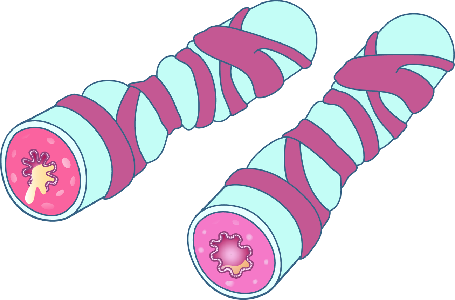

Detailreiche Fotografien aus der medizinischen Praxis ergänzen die Texte; moderne, genaue,

wissenschaftliche Zeichnungen geben Einblick in die Anatomie und die Funktion der Lunge und

anderer Organe.